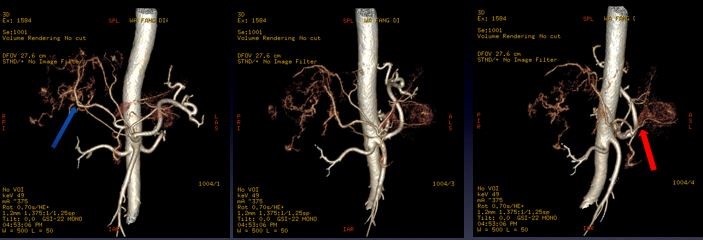

血管重建图像: 使用49keV图像观察,显示左右叶病灶丰富的血供情况 图中红、蓝箭头显示肝左右叶病灶分别来源于肝左右动脉

临床分析及诊断: 该患者有肠道间质瘤病史,病灶具有丰富的血供,血供来源一致,能谱分析肝左右叶病灶具有特征相似的能谱曲线,增强后不同于原发肝癌“快进快出”的强化特点,有逐渐延迟强化的趋势,考虑为肝脏的多发转移可能大。该病人于3周后手术治疗,病理结果证实为肠道间质瘤的多发肝转移。 小结:能谱曲线可更加直观的从病灶动脉期强化程度及持续时间对肝脏富血供占位进行鉴别,应用强化前后能谱曲线的高度和斜率变化来评估病变的血供特点,结合血管显示的最佳keV图像,可从多个角度反映病变特征,达到诊断和鉴别诊断的目的。 临床小知识: 胃肠道间质瘤(Gastrointestinal Stromal Tumors, GIST)是一类起源于胃肠道间叶组织的肿瘤,占消化道间叶肿瘤的大部分。Mazur 等于1983 年首次提出了胃肠道间质肿瘤这个概念。胃肠道间质瘤占胃肠道恶性肿瘤的1~3%,多发于中老年患者,GIST大部分发生于胃(50~70%)和小肠(20~30%),结直肠约占10~20%,食道占0~6%,肠系膜、网膜及腹腔后罕见。GIST病人20-30%是恶性的,第一次就诊时约有11~47%已有转移,转移主要在肝和腹腔。手术切除是胃肠道间质肿瘤首选且唯一可能治愈的方法,GIST高危患者术后复发转移率高,可达55%~90%,80%在术后1~2年内有3/4局部复发。 致谢:辽宁省瓦房店市中心医院